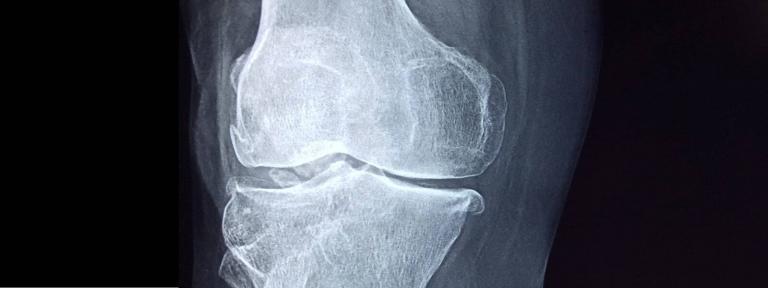

Адам ағзасынан бөлек сүйек тінін жасап шығаруға болама? Қазақстандық ғалымдар осыған жауап беретін бірегей жобаны бастады. Профессор Дана Ақылбекова жетекшілік еткен Назарбаев университетінің бір топ ғалымы адам сүйегін өсіріп оның 3D моделін басып шығаруға мүмкіндік беретін тың технология жасап шықты.